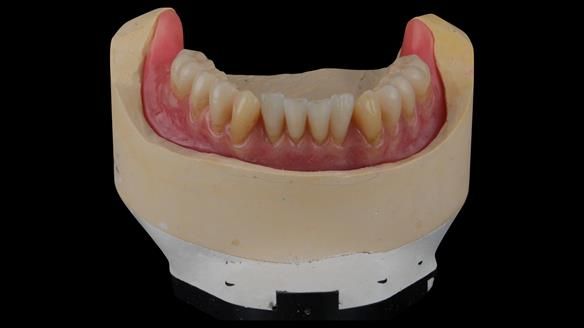

The clinical situation and treatment process is shown in detail below with photographs. I (Finlay Sutton) provided the clinical work and Rowan Garstang provided the technical work.